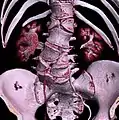

Sacralization of the L5 vertebra is seen at the lower right of the image.

Sacralization of the fifth lumbar vertebra (or sacralization) is a congenital anomaly, in which the transverse process of the last lumbar vertebra (L5) fuses to the sacrum on one side or both, or to ilium, or both. These anomalies are observed in about 3.5 percent of people, and it is usually bilateral but can be unilateral or incomplete (ipsilateral or contralateral rudimentary facets) as well. Although sacralization may be a cause of low back pain, it is asymptomatic in many cases (especially bilateral type). Low back pain in these cases most likely occurs due to biomechanics. In sacralization, the L5-S1 intervertebral disc may be thin and narrow. This abnormality is found by X-ray.